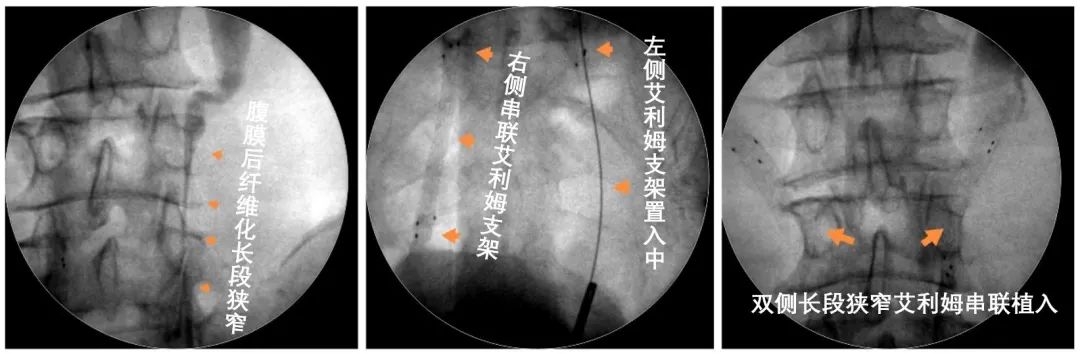

国际医生节 | “医”心为你:新型微创技术离别肾功效损伤 ——新华医院泌尿外科乐成开展多例Allium输尿管支架植入术